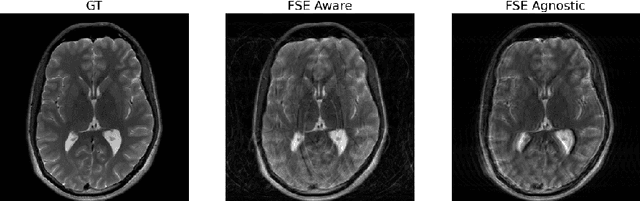

Abstract:Magnetic Resonance Imaging (MRI) is a widely used medical imaging modality boasting great soft tissue contrast without ionizing radiation, but unfortunately suffers from long acquisition times. Long scan times can lead to motion artifacts, for example due to bulk patient motion such as head movement and periodic motion produced by the heart or lungs. Motion artifacts can degrade image quality and in some cases render the scans nondiagnostic. To combat this problem, prospective and retrospective motion correction techniques have been introduced. More recently, data driven methods using deep neural networks have been proposed. As a large number of publicly available MRI datasets are based on Fast Spin Echo (FSE) sequences, methods that use them for training should incorporate the correct FSE acquisition dynamics. Unfortunately, when simulating training data, many approaches fail to generate accurate motion-corrupt images by neglecting the effects of the temporal ordering of the k-space lines as well as neglecting the signal decay throughout the FSE echo train. In this work, we highlight this consequence and demonstrate a training method which correctly simulates the data acquisition process of FSE sequences with higher fidelity by including sample ordering and signal decay dynamics. Through numerical experiments, we show that accounting for the FSE acquisition leads to better motion correction performance during inference.